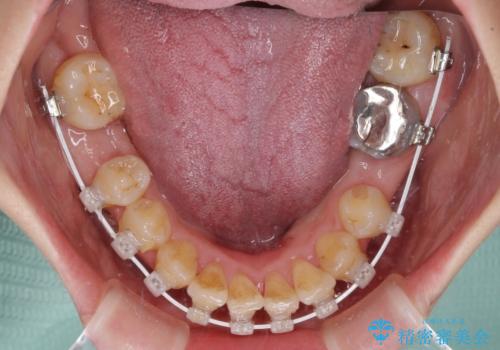

- 審美装置

口元の突出感とデコボコがあり、上下左右の小臼歯4本を抜歯して矯正治療を行う方針としました。(右上は欠損のため計3本抜歯)

むし歯となっている歯は状態が悪く、将来的に抜歯となる可能性が高かったため、定石で抜歯させる小臼歯の代わりにむし歯となっている大臼歯を抜歯し、ワイヤー装置にて矯正治療を行うこととしました。

イレギュラーな大臼歯抜歯矯正であったため、治療期間の長期化が想定されましたが、何とか3年ちょうどで終えることができました。